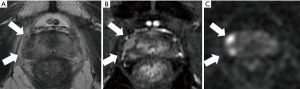

His care team excluded apparent distant metastasis per these evaluations that were available at that time, although the possibility of undetected micro dissemination could not be excluded. His care team conducted a template-guided saturation mapping (TGSM) biopsy at five-year intervals after EBRT completion. The MRI identified cancer recurrence in the right lobe of his prostate (Figure 1). Based on the MRI findings, his care team conducted a template-guided saturation mapping (TGSM) biopsy at five years interval after EBRT completion, collecting 30 samples, including the seminal vesicle. They identified poorly differentiated adenocarcinoma exclusively from the four biopsy samples of the right lobe of the prostate, which corresponded to the MRI findings (Figure 1 and Table 2). No cancer cells were located in the remaining 26 TGSM biopsy samples where prostate tissue was replaced by fibromuscular tissue indicating an EBRT effect. Based on these findings, his care team conducted salvage LDR BT with a radiation dose of 160 Gy via 125I seeds implantation to cover the MRI- and biopsy-positive lesion. The rectal volume receiving 100% of the prescribed minimal peripheral dose (R100) was 0 cc. Figure 2 presents the intraoperative dose cloud image. The dosimetric parameters of the salvage LDR BT intraoperatively and one month later are shown in Table 2 and Table 3, respectively. He experienced Grade 2 genitourinary (GU) toxicity at four months and Grade 1 gastrointestinal (GI) toxicity eight months after salvage LDR BT.

The MRI identified prostate cancer recurrence in the left posterior corner on the mid portion of the prostate (Figure 3). His care team conducted a TGSM biopsy based on the MRI findings at six-year intervals after EBRT completion, collecting 31 samples, including the seminal vesicle. They identified poorly differentiated adenocarcinoma from four biopsy samples from the left lower corner of the prostate, which corresponded to the MRI findings (Table 4). No cancer cells were located in the remaining TGSM biopsy samples where prostate tissue was replaced into fibromuscular tissue indicating EBRT effect.